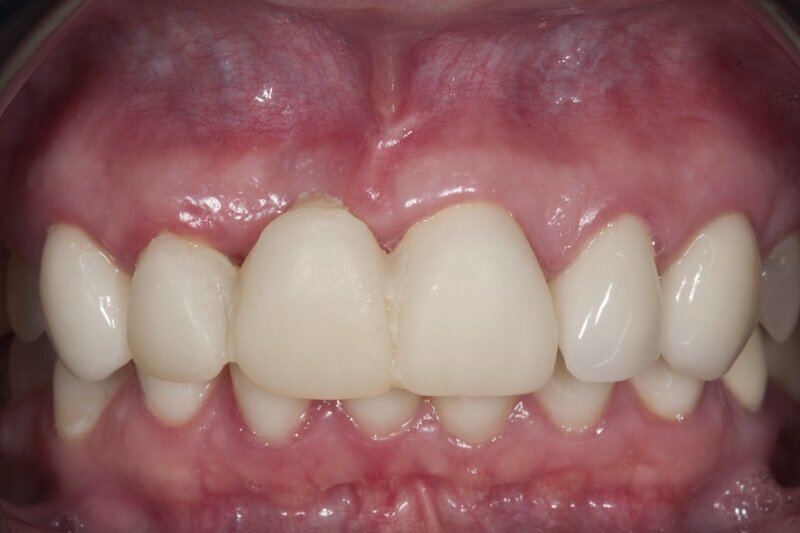

Po zabiegu pacjentka nie przyjmowała żadnych leków, także przeciwbólowych. Zgłosiła się na wizytę kontrolną 7 dni później. Badanie wewnątrzustne wykazało pokrycie nabłonkiem odsłoniętej w czasie zabiegu okostnej i znaczny stopień wygojenia rany (Ryc. 8), co umożliwiło usunięcie szwów.

Po kolejnych 4 tygodniach wykonano zabieg bocznej regeneracji kostnej wyrostka zębodołowego w okolicy utraconego zęba 11 w przygotowaniu do przyszłej implantacji (Ryc. 9-11). Zastosowano biomodulację przy użyciu głowicy Genova, na rycinie 12 pokazano stan tkanek 3 tygodnie po zabiegu.

Ryc. 9_Stan 7 dni po zabiegu.

Ryc. 13_Stan 3 tygodnie po zabiegu regeneracyjnym.